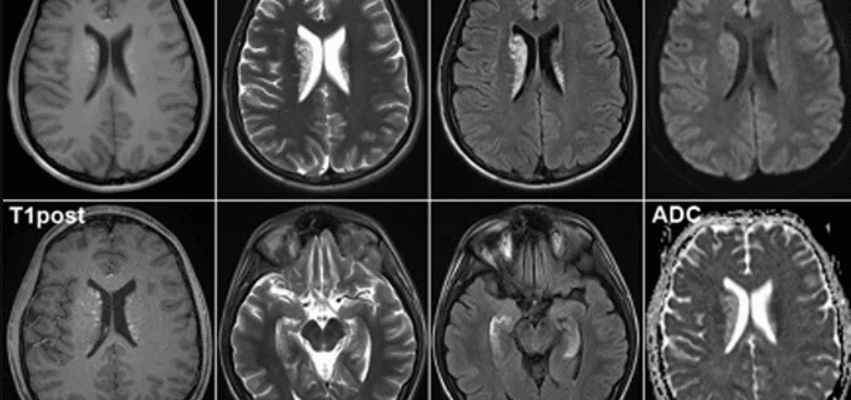

Магнітно-резонансна томографія (МРТ) – це медичний інструмент, який використовує потужний магніт, радіочастотні хвилі та комп’ютер для отримання чітких зображень внутрішніх органів. Процедура, що виглядає натисненням кнопки, але завдяки якій лікарі можуть проникнути до найглибших, найпотаємніших куточків людського тіла.

- МРТ без контрасту: чудово підходить для загального обстеження. Добре для початку, для швидкого огляду без зайвих ускладнень.

- МРТ з контрастом: тут уже інша справа, серйозніше. Підходить для виявлення пухлин, судинних аномалій і інших “злидників”, які ховаються вдало.